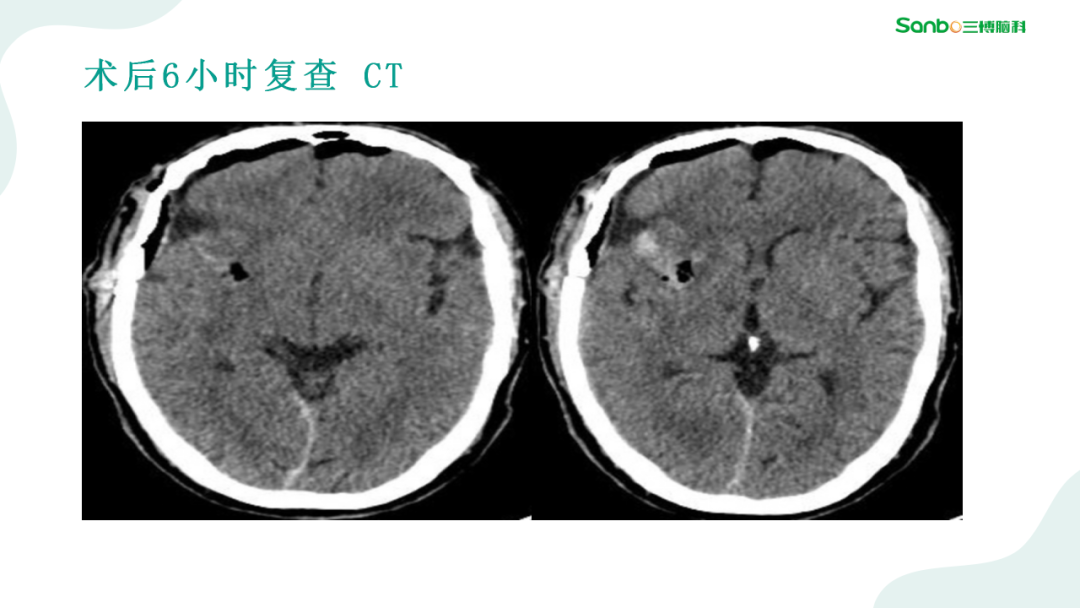

2月28日下午3:00,第二期“健康小课堂”科普活动由神外二科副主任杨海洋围绕《脑血管病的那些事》,给大家耐心讲解了有关脑血管的相关知识,生动的讲课引发在场的热烈讨论,大家纷纷表示受益匪浅。